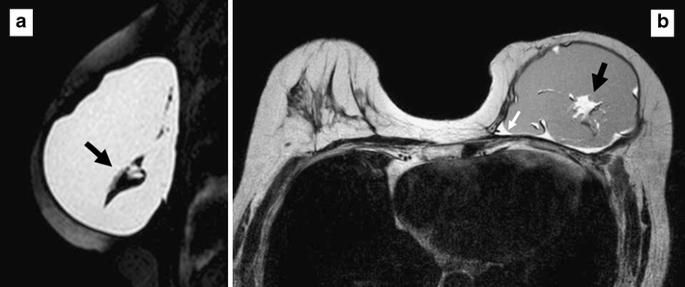

一块移除的已用20年的乳房假体。在其背面(B)可以看到多处孔洞(黑色箭头)以及假体收缩形成的褶皱(白色箭头)。© ResearchGate